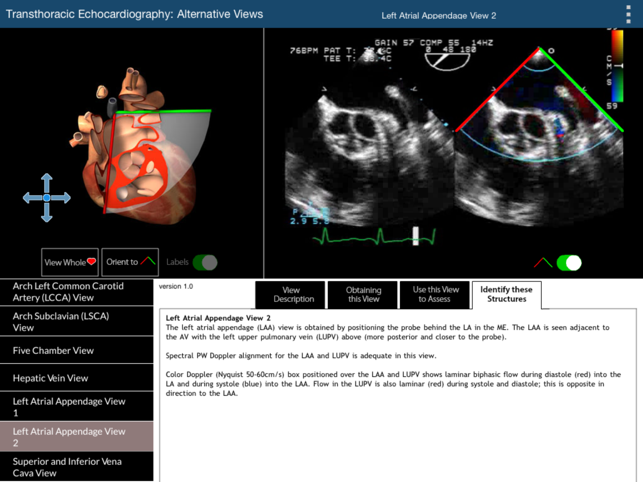

The primary challenge in learning TEE is translating the two dimensional echocardiographic image into a visualization of the complex three-dimensional (3D) structure of the heart. This TEE Alternative Views app provides a learning environment where users can explore 19 non-standard but complimentary 2D TEE views using two visualization methods simultaneously: (1) a rotatable 3D heart model with an echocardiographic plane and (2) the associated TEE clip. The 3D heart model and echo plane can be rotated, helping to relate the echocardiographic image to heart structures. Part of the heart above the echo plane can be removed, revealing the internal cardiac structures that correspond to the TEE image. This app will enable the user to perform a more complete TEE study than can be obtained from the 20 standard TEE views. For the 20 standard TEE views, please refer to our TEE Standard Views app. The 19 alternative TEE views illustrated in this app are: Coronary Sinus View (100 Degrees) Cor